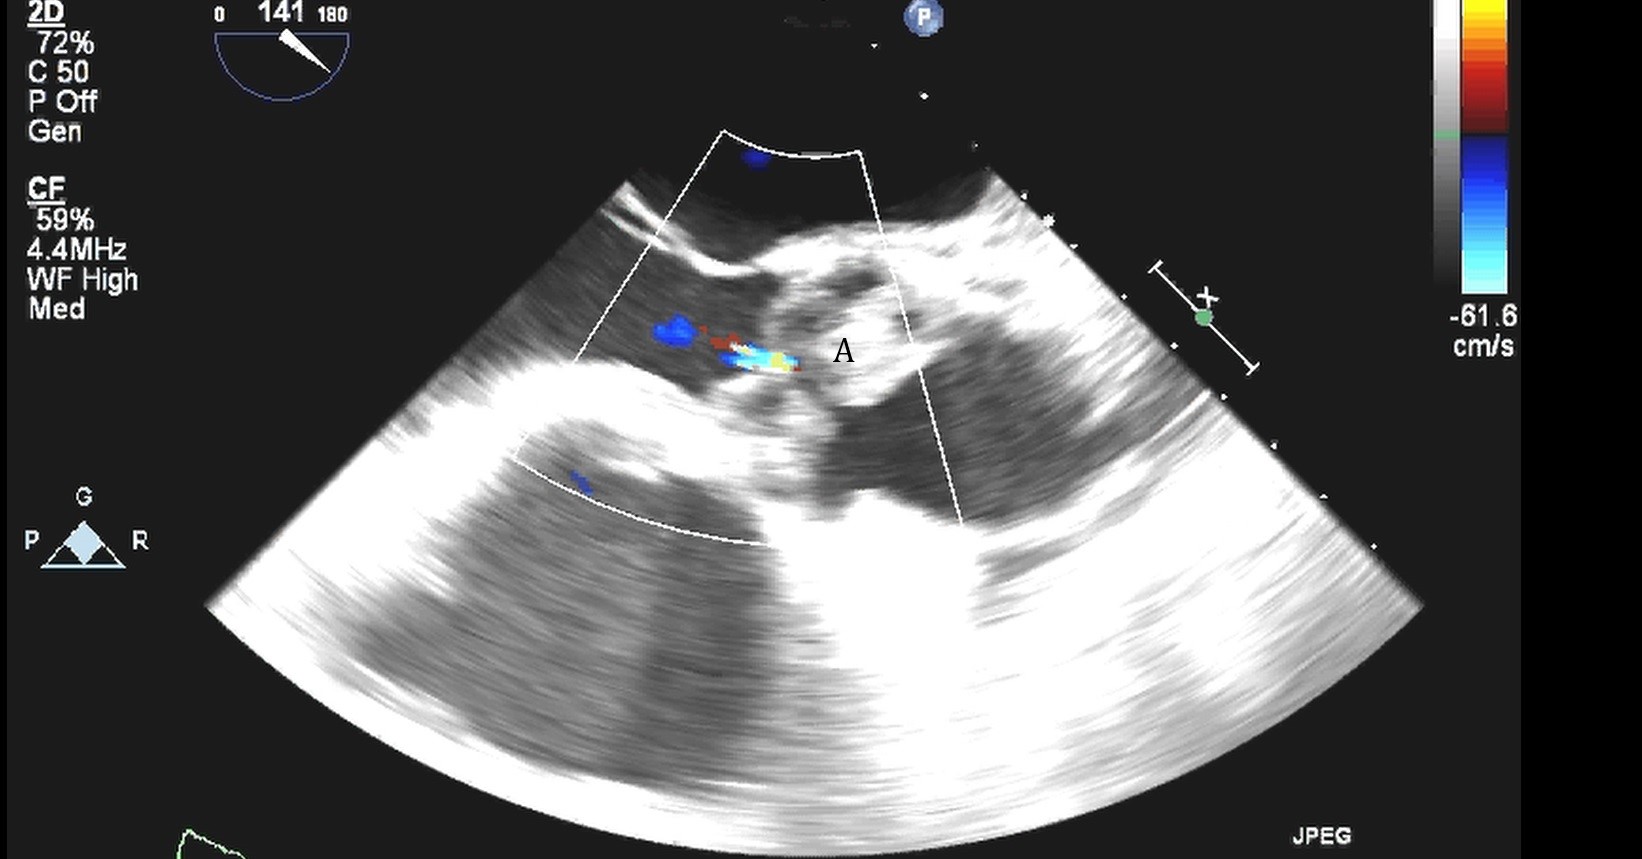

After initial access is obtained with a guidewire, TEE can confirm placement of the guidewire within the aorta and ensure there is no iatrogenic dissection from the procedure. The midesophageal long axis and 4 chamber views can be used to visualize the guidewire crossing of the aortic valve and positioning within the LV cavity. The wire tip should point towards the LV apex. Wire placement too deep within the LV can trigger ventricular arrhythmias and tethering of the mitral valve or subvalvular apparatus should be avoided as this can result in the inlet abutting the mitral valve or damage to subvalvular apparatus (Figs. 3,4) [13]. When the proceduralist is advancing the Impella over the guidewire, the best view to observe the device crossing the aortic valve is the midesophageal long axis view [13].

Impella (A) in the LV cavity caused disruption and damage to subvalvular apparatus resulting in flail segment (B) of the mitral valve.

Fig. 4.Impella (A) placement causing disruption and damage to subvalvular apparatus resulting in mitral valve flail (B) and mitral regurgitation (C).